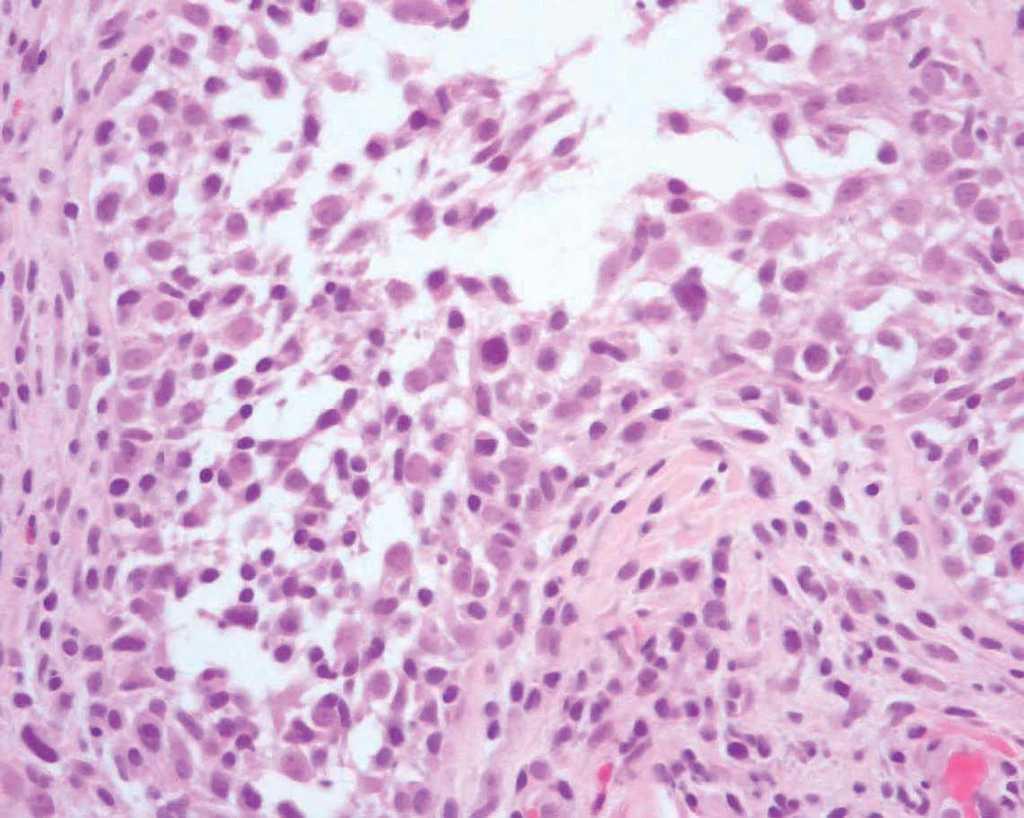

Varias biopsias cutáneas tomadas de distintas localizaciones presentaban, como característica común, la presencia de densos infiltrados linfocitarios dérmicos constituidos por células de tamaño pequeño-interme-dio con núcleos hipercromáticos y cerebriformes con marcada tendencia a la distribución perifolicular y ocasionales linfocitos que infiltraban el epitelio folicular (fig. 2). Algunos folículos se acompañaban de mucinosis folicular (fig. 3). Destacaba la presencia de densos infiltrados linfocitarios, semejantes a los perifoliculares, que se localizaban en íntimo contacto con los ovillos ecrinos con infiltración ocasional del epitelio ductal (fig. 4).

Fig. 2.—Infiltrado linfoide atípico en el interior de un folículo piloso. (Hematoxilina-eosina, ×200.)